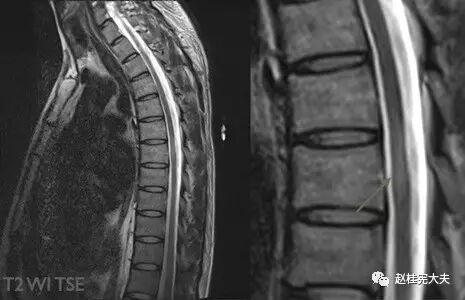

图16. 示C2-6水平颈髓内散在小斑片状T2较高信号,箭头示C4-5水平结节状高信号灶。

图17. 示T5水平胸髓内见短节段椭圆形病灶,T2高信号。

图18. 示T7-8水平胸髓内见条片状T2高信号,且<2个椎体节段。

视神经受侵犯时,呈现T2高信号并可伴视神经增粗,与单纯MS相比,NMO视神经病变范围更广泛,可延伸到视神经后部甚至视交叉,且病变通常呈对称性分布[3];MS脊髓受累者,病灶多>3 mm且<2个椎体节段,横断面上<1/2脊髓面积且水肿轻,而NMOSD脊髓病变可扩展到3个以上脊髓水平,但部分亚洲MS患者的脊髓病灶长度可≥2个椎体节段,AQP4抗体检测有助于鉴别。